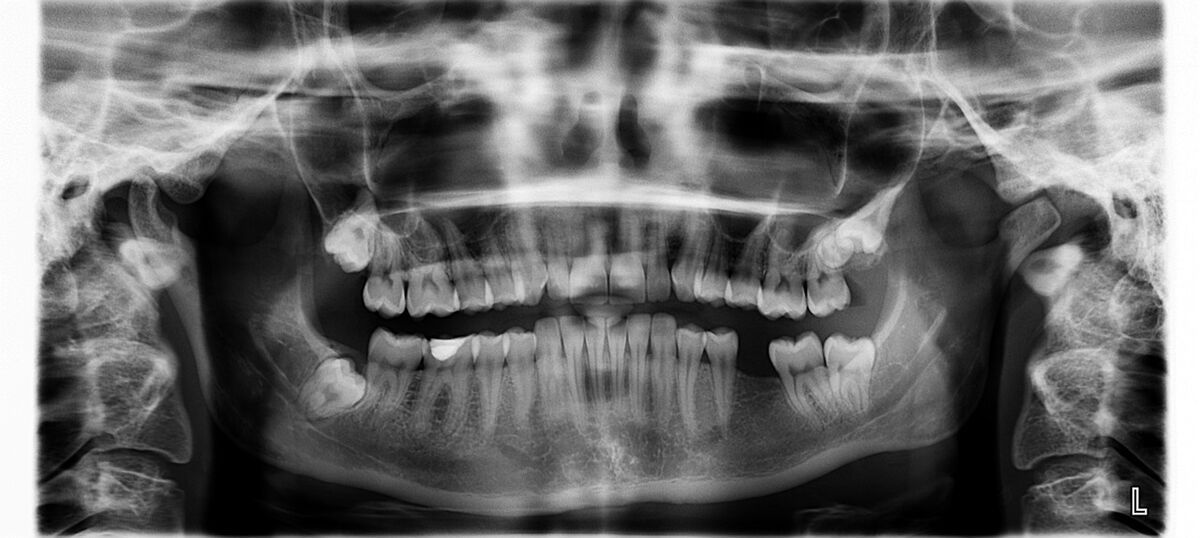

Radiologia wczesnych okresów rozwojowych (7-12 lat) dla stomatologa ogólnie praktykującego

17.00 - 18.30 - Radiologia wczesnych okresów rozwojowych ( 7-12 lat) dla stomatologa ogólnie praktykującego - dr n.med. Małgorzata Kuc-Michalska